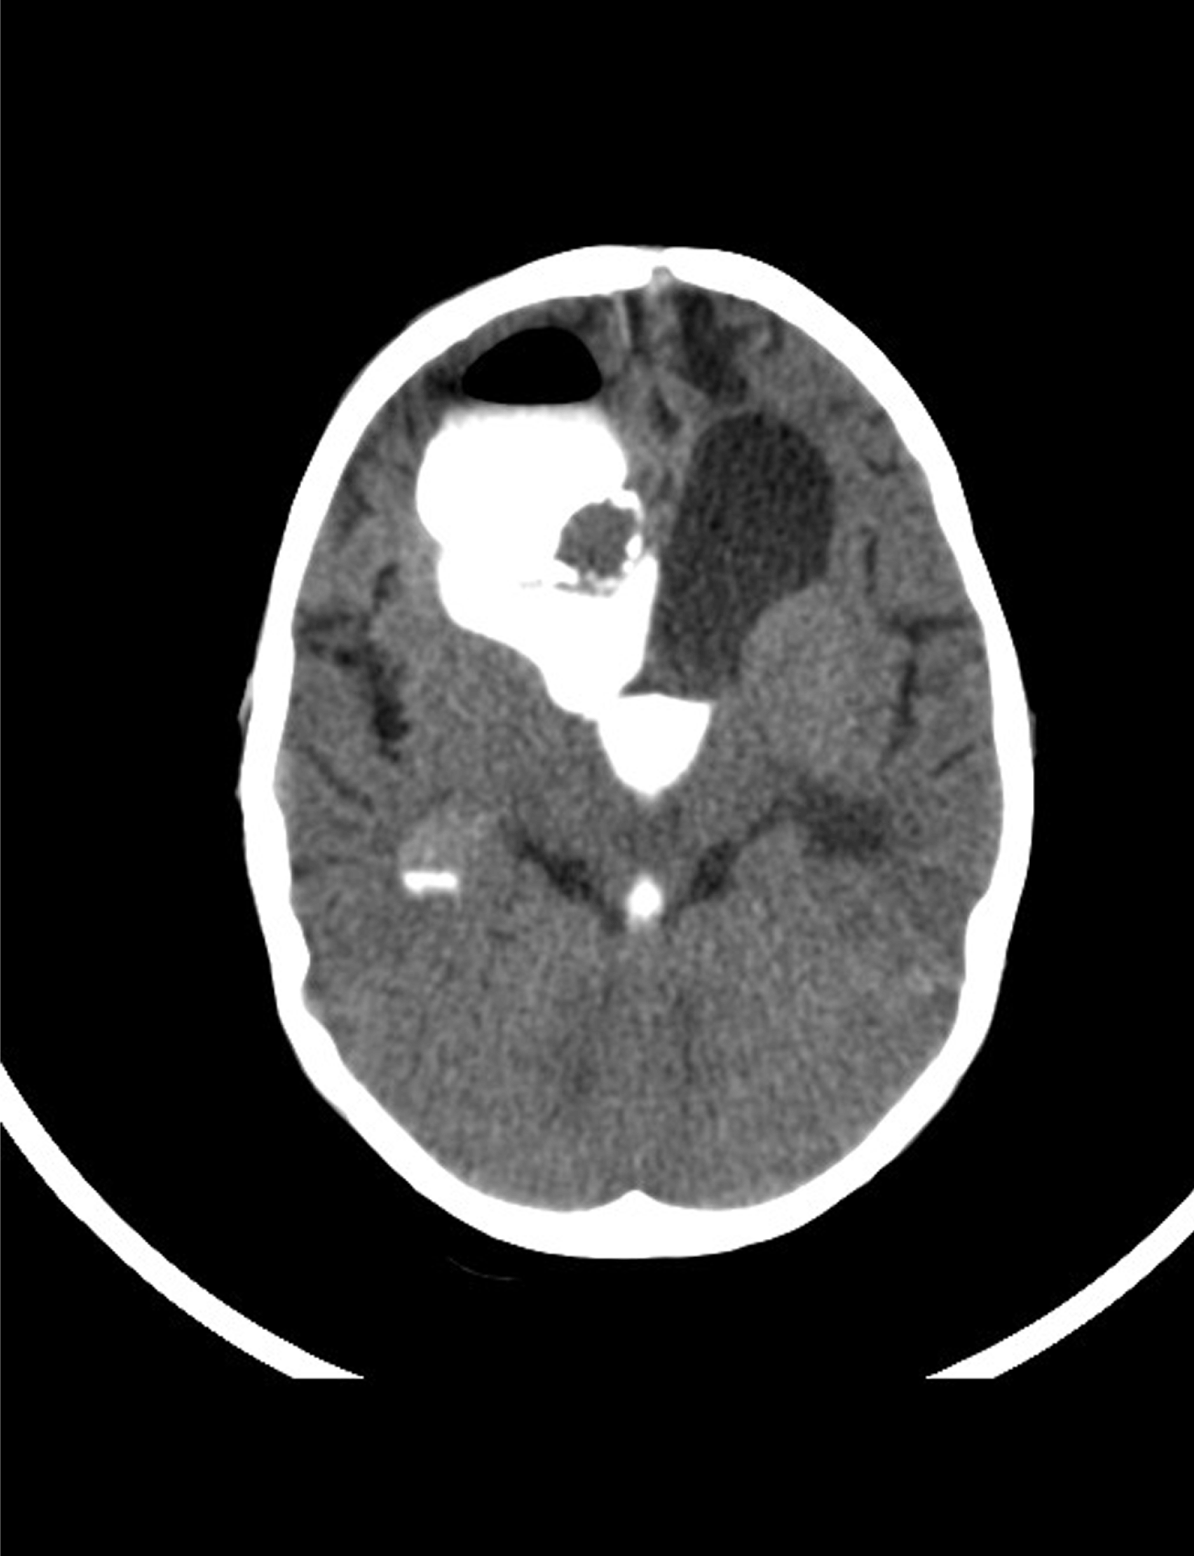

An eight-year-old boy was referred by an ophthalmologist to the Pediatric Oncology Center (Cape Town) in 2004. He presented with features of hypopituitarism and bilateral optic atrophy. His imaging studies showed a ring enhancing lesion with solid and cystic components arising from the suprasellar area and compressing the third ventricle (V3) with associated hydrocephalus. A subtotal resection and left subdural shunt was performed at that time, and a histological diagnosis of CP was made hormonal replacement was initiated. A year later following his first recurrence the patient was treated with repeat debulking resection and at this time an Ommaya reservoir was placed. Further subtotal resection to the growing lesion, followed by adjuvant radiotherapy (54 Gy) was done the following year after he had turned three years old. At this point, multi-modality treatment allowed for disease stability for another three years, when evidence of disease progression was again noted. This prompted surgical re-intervention and a debulking procedure was again performed. In June 2011, at the age of eight, radiological evidence of tumor recurrence was again noted (Figure 1A-B) and after multi-disciplinary discussion, treatment with intracystic IFNa-2b was proposed as an alternative method of gaining local control and thereby controlling disease progression. A pre-treatment leakage test was done via the Ommaya reservoir and this showed extensive leakage around the catheter into the right ventricle. (Figure 2) There was thus concern over the potential for leakage during IFNa-2b treatment and the clinical implications of this were researched. The treating multi-disciplinary team enlisted further advice from international colleagues regarding the safety of IFNa-2b administration in such a situation. Following this advice and the information obtained through documented research, a decision was made to proceed with the therapy as intra-ventricular spillage of IFNa was considered to be innocuous. The first cycle was given intratumorally at a dose of 3,000,000 international units. This dose was then administered three times a week for a total of four weeks. During these treatment sessions, the patient exhibited severe lethargy. Two weeks after completing the full planned course he presented with confusion, urinary incontinence and was found to have hypernatremia and hyperthyroidism. Magnetic resonance imaging (MRI) of the brain, at that point revealed significant brain atrophy, striking volume loss with no significant change in the tumor size and an increase in hydrocephalus. (Figure 3A-B) The patient was admitted and his condition stabilized following appropriate management. His hormonal replacement medications were adjusted and a shunt was inserted to drain the re-accumulating hydrocephalus. He was seen again in the combined Pediatric Neuro-Oncology clinic a month later, and was clinically stable. It was thus decided to forgo further IFNa-2b therapy due to concern about further complications. He will thus be followed at regular intervals for symptom control and monitoring of his endocrine functions. | ||||||